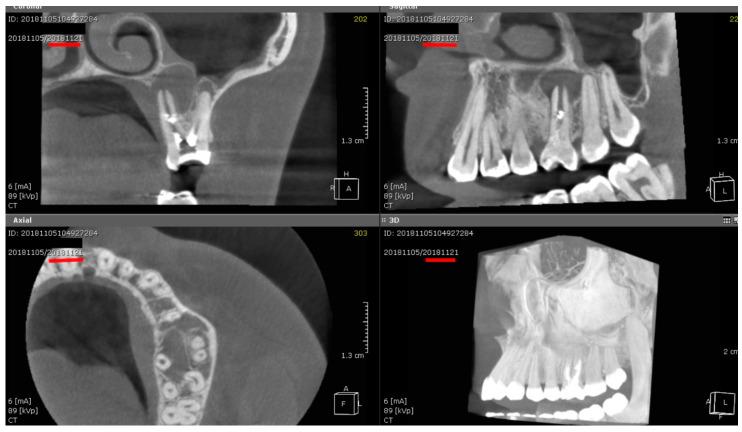

: Periapical healing and bone regeneration are key indicators of endodontic success. This study evaluated the effectiveness of laser-assisted disinfection compared to conventional chemical irrigation in promoting periapical healing across various bone densities (D1-D5), using cone-beam computed tomography (CBCT) over multiple follow-up intervals. : A total of 120 patients with radiographically confirmed periapical lesions were enrolled and allocated into two groups: an experimental group ( = 60, chemical irrigation + Er,Cr:YSGG laser disinfection) and a control group ( = 60, chemical irrigation only). CBCT scans were obtained at 6 months, 1 year, 2 years, and 2.5 years post-treatment to assess lesion size and CBCT-PAI scores. Lesions were classified radiographically as either or periapical radiolucencies. Paired -tests and ANOVA were used for statistical comparisons. : The experimental group demonstrated significantly greater reductions in lesion size and improvements in CBCT-PAI scores at all time points. Healing was especially enhanced in low-density bone (D4-D5). Complete healing rates were higher in the laser group for (89.5% vs. 68.4%) and (81.8% vs. 59.1%). Post hoc power analysis confirmed statistical reliability (Cohen's d = 3.48; power > 0.99). : Laser-assisted endodontic disinfection significantly accelerates periapical healing and promotes bone regeneration, particularly in low-density bone. CBCT imaging supports its clinical superiority over conventional irrigation methods.

根尖周愈合和骨再生是牙髓治疗成功的关键指标。本研究使用锥形束计算机断层扫描(CBCT)在多个随访期内,评估了与传统化学冲洗相比,激光辅助消毒在促进不同骨密度(D1-D5)的根尖周愈合方面的有效性。

总共纳入了120例经影像学证实有根尖周病变的患者,并将其分为两组:实验组(n = 60,化学冲洗 + Er,Cr:YSGG激光消毒)和对照组(n = 60,仅化学冲洗)。在治疗后6个月、1年、2年和2.5年进行CBCT扫描,以评估病变大小和CBCT-PAI评分。病变在影像学上被分类为根尖周透射影或根尖周透射影。采用配对t检验和方差分析进行统计学比较。

实验组在所有时间点的病变大小减少和CBCT-PAI评分改善方面均显示出显著更大的效果。在低密度骨(D4-D5)中愈合尤其增强。激光组的完全愈合率在根尖周透射影(89.5% 对 68.4%)和根尖周透射影(81.8% 对 59.1%)方面更高。事后功效分析证实了统计可靠性(Cohen's d = 3.48;功效 > 0.99)。

激光辅助牙髓消毒显著加速根尖周愈合并促进骨再生,特别是在低密度骨中。CBCT成像支持其相对于传统冲洗方法的临床优越性。